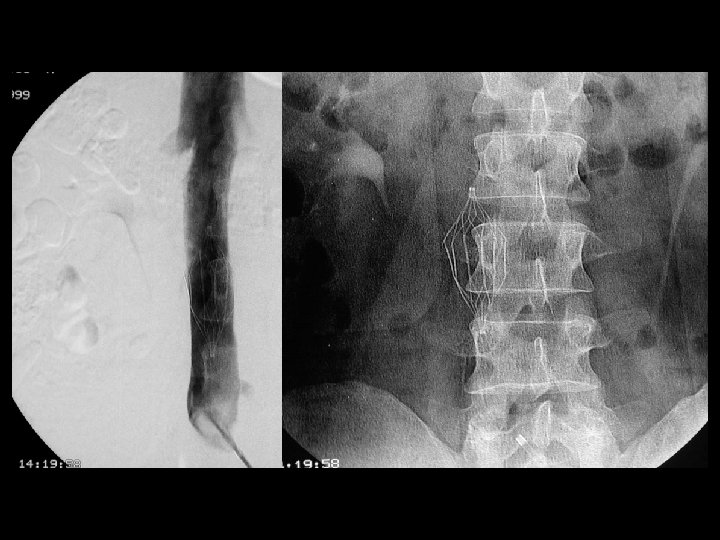

Endogreft üEndovasküler uygulanan greft üCerrahi eksplorasyon+endovasküler teknik üAnevrizma tedavisi+vasküler rekonstrüksiyon üTorakal aorta anevrizması üAbdominal aorta anevrizması üİliak arter anevrizması

Infrarenal Abdominal Aort Anevrizması; Endogreft ile tedavi